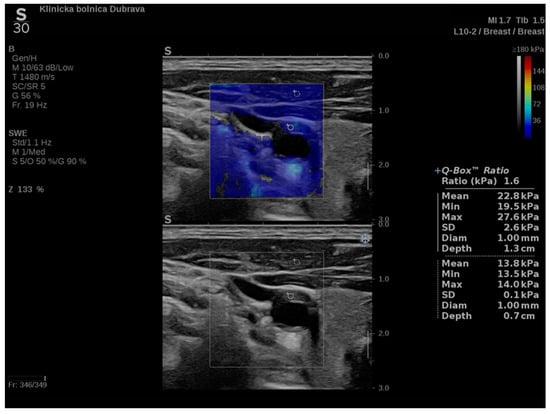

In addition to conventional, Doppler and contrast-enhanced ultrasonography, elastography techniques are another area where ultrasound is being increasingly used, this time to assess the elastic properties of the insonated tissue. There are two types of ultrasound elastography: strain and shear wave elastography (SWE). Strain elastography is performed by manual compression using the transducer, which then produces an image based on the resulting displacement of the tissue caused by the compression. However, it is difficult to measure the exact amount of the applied force during compression, resulting in the method being difficult to standardize. Additionally, the absolute elasticity values cannot be calculated, and only qualitative results can be obtained. Unlike strain elastography, SWE is a type of ultrasound elastography where the elastic properties of the insonated tissues can be expressed both qualitatively and quantitatively (Figure 1 and Figure 2) [22].

Figure 1. An example of an ultrasound examination with shear wave elastography of a segment of the distal right CCA in the longitudinal view with B-mode ultrasound at bottom and shear wave elastography at the top where the elastic properties of the examined tissues (carotid artery wall and surrounding soft tissues) are displayed qualitatively by benign color-coded and superimposed on the B-mode image. Red color denotes the stiffest areas with the highest elastic modulus values.